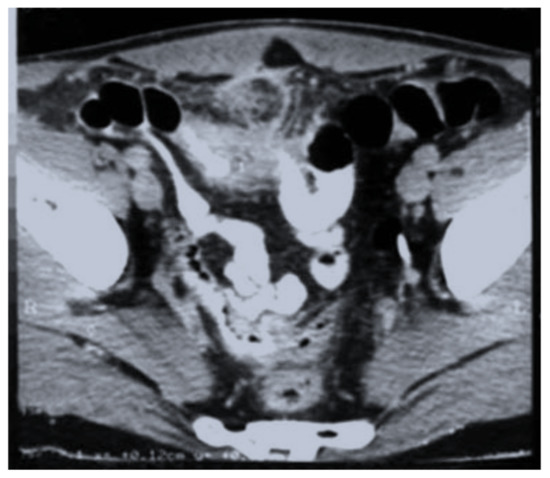

The disease was rarely suspected on imaging and was usually noncontributory to the positive diagnosis. The abdominal ultrasound (Figure 1) described collections and abscesses found in the abdomen and pelvis, and there was also inflammatory involvement or a solid, heterogeneous mass, surrounded by collections confirmed by CT findings of the abdomen and pelvis (Figure 2), which showed the infiltrative nature of the disease, a heterogeneous mass involving a distal ileum, cecum, and ascending or transverse colon, and an inflammatory mass involving the ovaries for a pelvic tumor. Lab work revealed an elevated white count and anemia, and tumor markers were normal or with slightly modified values in most cases. We did not use polymerase chain reaction (PCR) for diagnosis.

Figure 2.

CT scan—heterogeneous mass involving distal ileum; inflammatory changes of the mesentery were also observed.